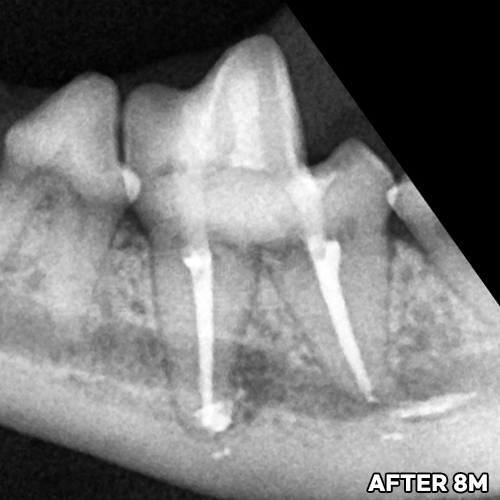

[턱뼈를 녹이는 심한 치근단농양을 신경치료로 치료 한 후 8개월 경과]

샘플